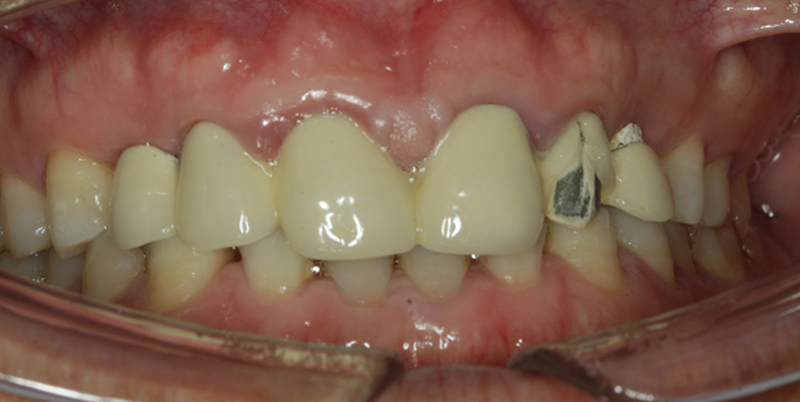

現(xiàn)病史:左側(cè)烤瓷牙崩瓷,影響美觀

檢查:22烤瓷牙表面崩瓷,13、23、24缺失

1、不良修復(fù)體松動(dòng)脫落,崩瓷;